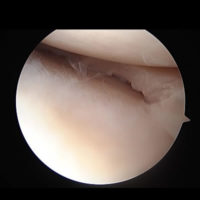

靱帯再建術(ACL)(前十字靱帯損傷)

関節鏡を用いて、ご自身の身体の下記部位の腱組織を使用し、新たな靱帯を作り直す再建術を行います。

当科では、靱帯成分をより広く、適正な位置に再現するために靱帯を2本再建する2重束再建を行っています。